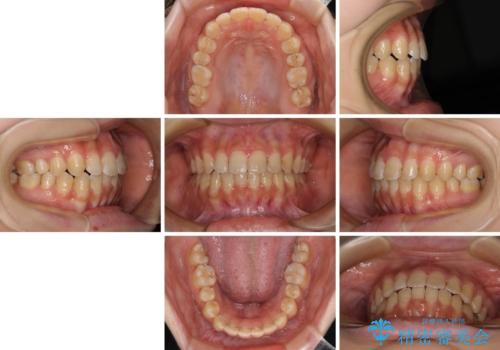

- 大学病院にて装置を装着したものの、治療が十分に受けることができないとのことで転院をされた患者様です。

上顎歯列が前方にあり、口元が閉じにくくなっていたため、既に装着されている装置を使用して上顎歯列全体を後方に移動させていくこととしました。

舌の突出癖があり、それが原因で上下前歯に隙間ができていたため、改善のためのトレーニングを行うように指示をしました。

舌の突出癖の影響か、なかなかスペースが閉じきらず、治療期間は予定よりも長期間となりました。

舌突出癖改善のトレーニングの重要性を認識することとなりました。